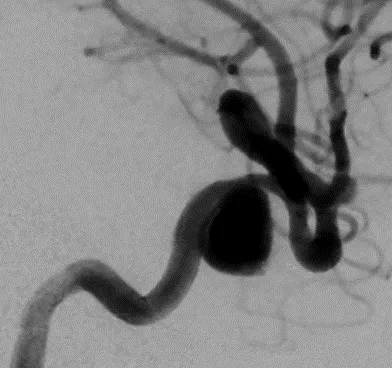

脳動脈瘤コイル塞栓術:破裂前交通動脈瘤

治療前の左内頸動脈造影、前交通動脈瘤に造影剤が入ります。

脳動脈瘤の中に、細いカテーテル(マイクロカテーテル)を誘導(この例では2本誘導しています)、プラチナ製の柔らかな糸状のコイルで脳動脈瘤の中を埋めていきます。左の写真はコイルを入れたのち、コイルが血管に、はみ出していないかを造影剤を流して確認します。右の写真はコイルの形状が左よりわかりやすい写真になっています。

コイルの充填により脳動脈瘤内に造影剤が入らなくなりました。